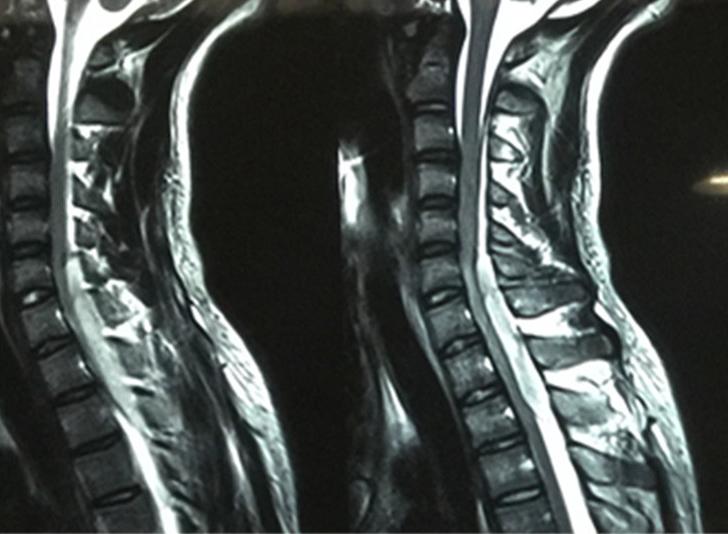

入院后拟给予患者静脉溶栓治疗,患者突然右下肢肌力降至1级,左下肢肌力也降至2级,T8以下皮肤出现痛觉减退,双侧Babinski征(+),患者自诉入院时颈部较前稍僵硬,医生未询问,自己也未告知,现后颈部疼痛明显,立即行头颅MRI及颈胸段MRI,结果提示:C6-T2脊髓硬膜外血肿。C6-T2椎体水平,矢状位T1加权像呈低信号,T2加权像显示高信号,见下图。

MRI是SSEH的首选影像学检查,MRI能更准确地了解血肿的节段、范围,脊髓压迫的严重程度以及脊髓水肿情况。SSEH在MRI上,矢状面上常表现为呈条梭状,在横断面上常呈新月形,甚至可以清楚看见被压缩的硬脑膜介于血肿和脊髓之间,在密度上,急性出血常表现为T1像呈等密度,T2像呈高密度,亚急性出血T1像呈高密度,T2像呈等低密度,增强一般不明显[4]。大多专家认为一旦确诊应立即考虑手术治疗[5]。在出现完全性瘫痪12小时以内进行手术治疗,脊髓功能多可恢复,大于48小时则会造成脊髓不同程度的不可逆损伤,难以恢复[6]。手术目的以尽快清除血肿,减轻脊髓压迫为主,同时可探查椎管内有无活动性出血,最终可以减轻神经功能缺损症状[7]。但也有报道称保守治疗可获得一定效果[8]。